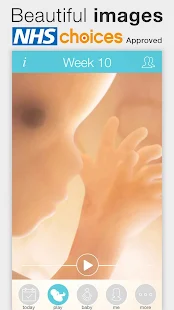

Pregnant? Get the worldwide No.1 Pregnancy App. Approved by the NHSWant to see beautiful, interactive images for every week of your pregnancy? Join more than 4 million users who already use this Pregnancy App to follow their pregnancy.

Our Pregnancy+ App can also be personalized for dads, grandparents and other family members.

Many happy parents and healthcare providers find this App easy to use and very informative.

- Pregnancy week by week info